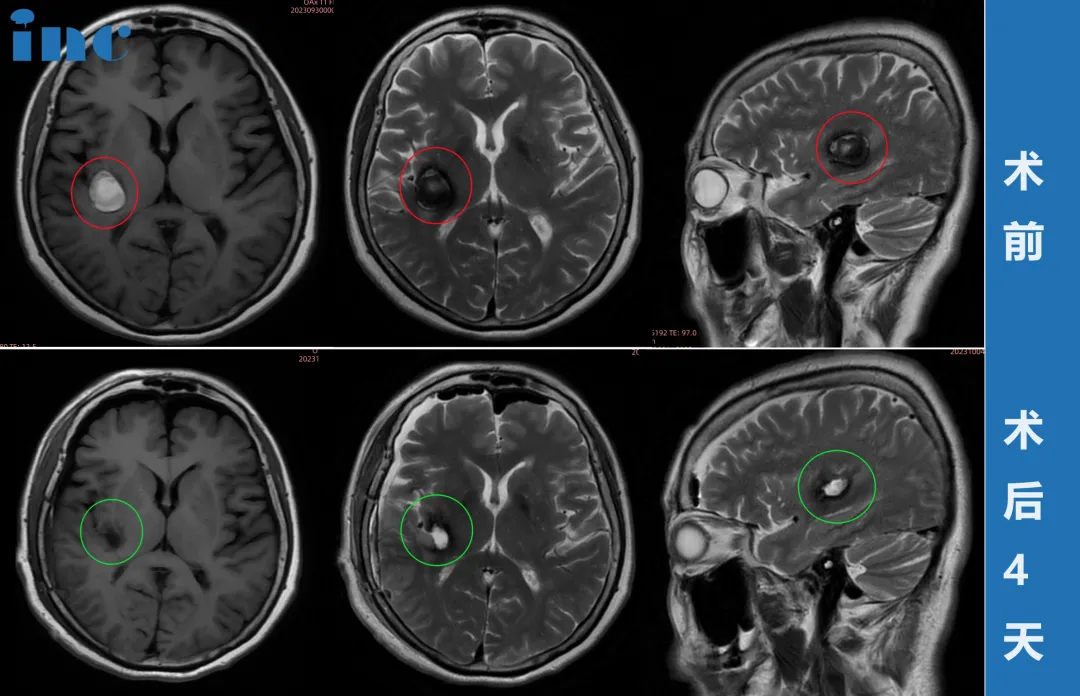

教授的责任感与担当消除了柯女士和家人的顾虑。9月29日视频咨询,30日患者从东北飞往苏州,10月1日国庆节当天,由巴教授主刀,国内神经外科团队配合,成功完成手术。术后核磁显示海绵状血管瘤完全切除,无新发神经功能损伤。

术前,巴教授告知最坏可能结果是左手无力,因此患者术后醒来第一反应就是活动左手。当发现手指活动灵活时,她彻底放心。令人惊喜的是,教授担忧的高龄患者常见脑萎缩问题并未出现,患者脑部状态优于同龄人,为手术成功提供了有利条件。